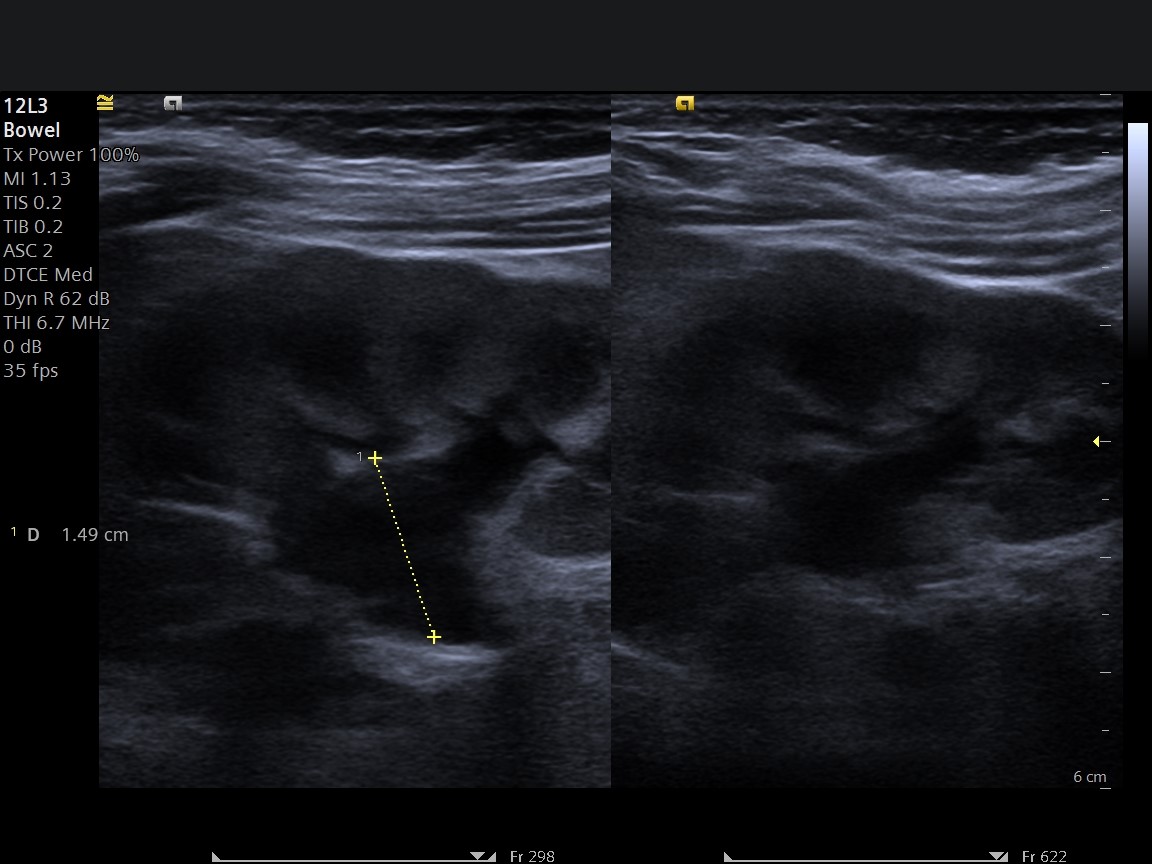

Ultrason ile UP Darlık Tanısı

UP darlık ultrason incelemesi:

- Böbrekte genişlemeyi (hidronefroz) gösterir

- İlk ve en önemli tanı yöntemidir

- Radyasyon içermez

- Güvenli ve tekrarlanabilir

👉 Özellikle deneyimli bir radyoloji uzmanı tarafından yapılan detaylı böbrek ultrasonu, UP darlığın erken teşhisinde kritik rol oynar. İncelemelerin tecrübeli bir hekim tarafından yapılıp rehberlerde tariflenen şekilde ölçümlerin yapılması ve bunların raporda belirtilmesi tanı ve takipte kritik önem taşır. Zira bu hastaların takiplerinin de aynı hekim tarafından yapılması yararlı olabilir.

Ultrasonun UP Darlıktaki Önemi

UP darlık ultrasonu:

✔ Erken dönemde hastalığı yakalar

✔ Böbrek hasarı oluşmadan tanı koydurur

✔ Hastalığın takibinde kullanılır

👉 Ultrasonun başarısı, cihazdan çok yapan hekimin tecrübesine bağlıdır.